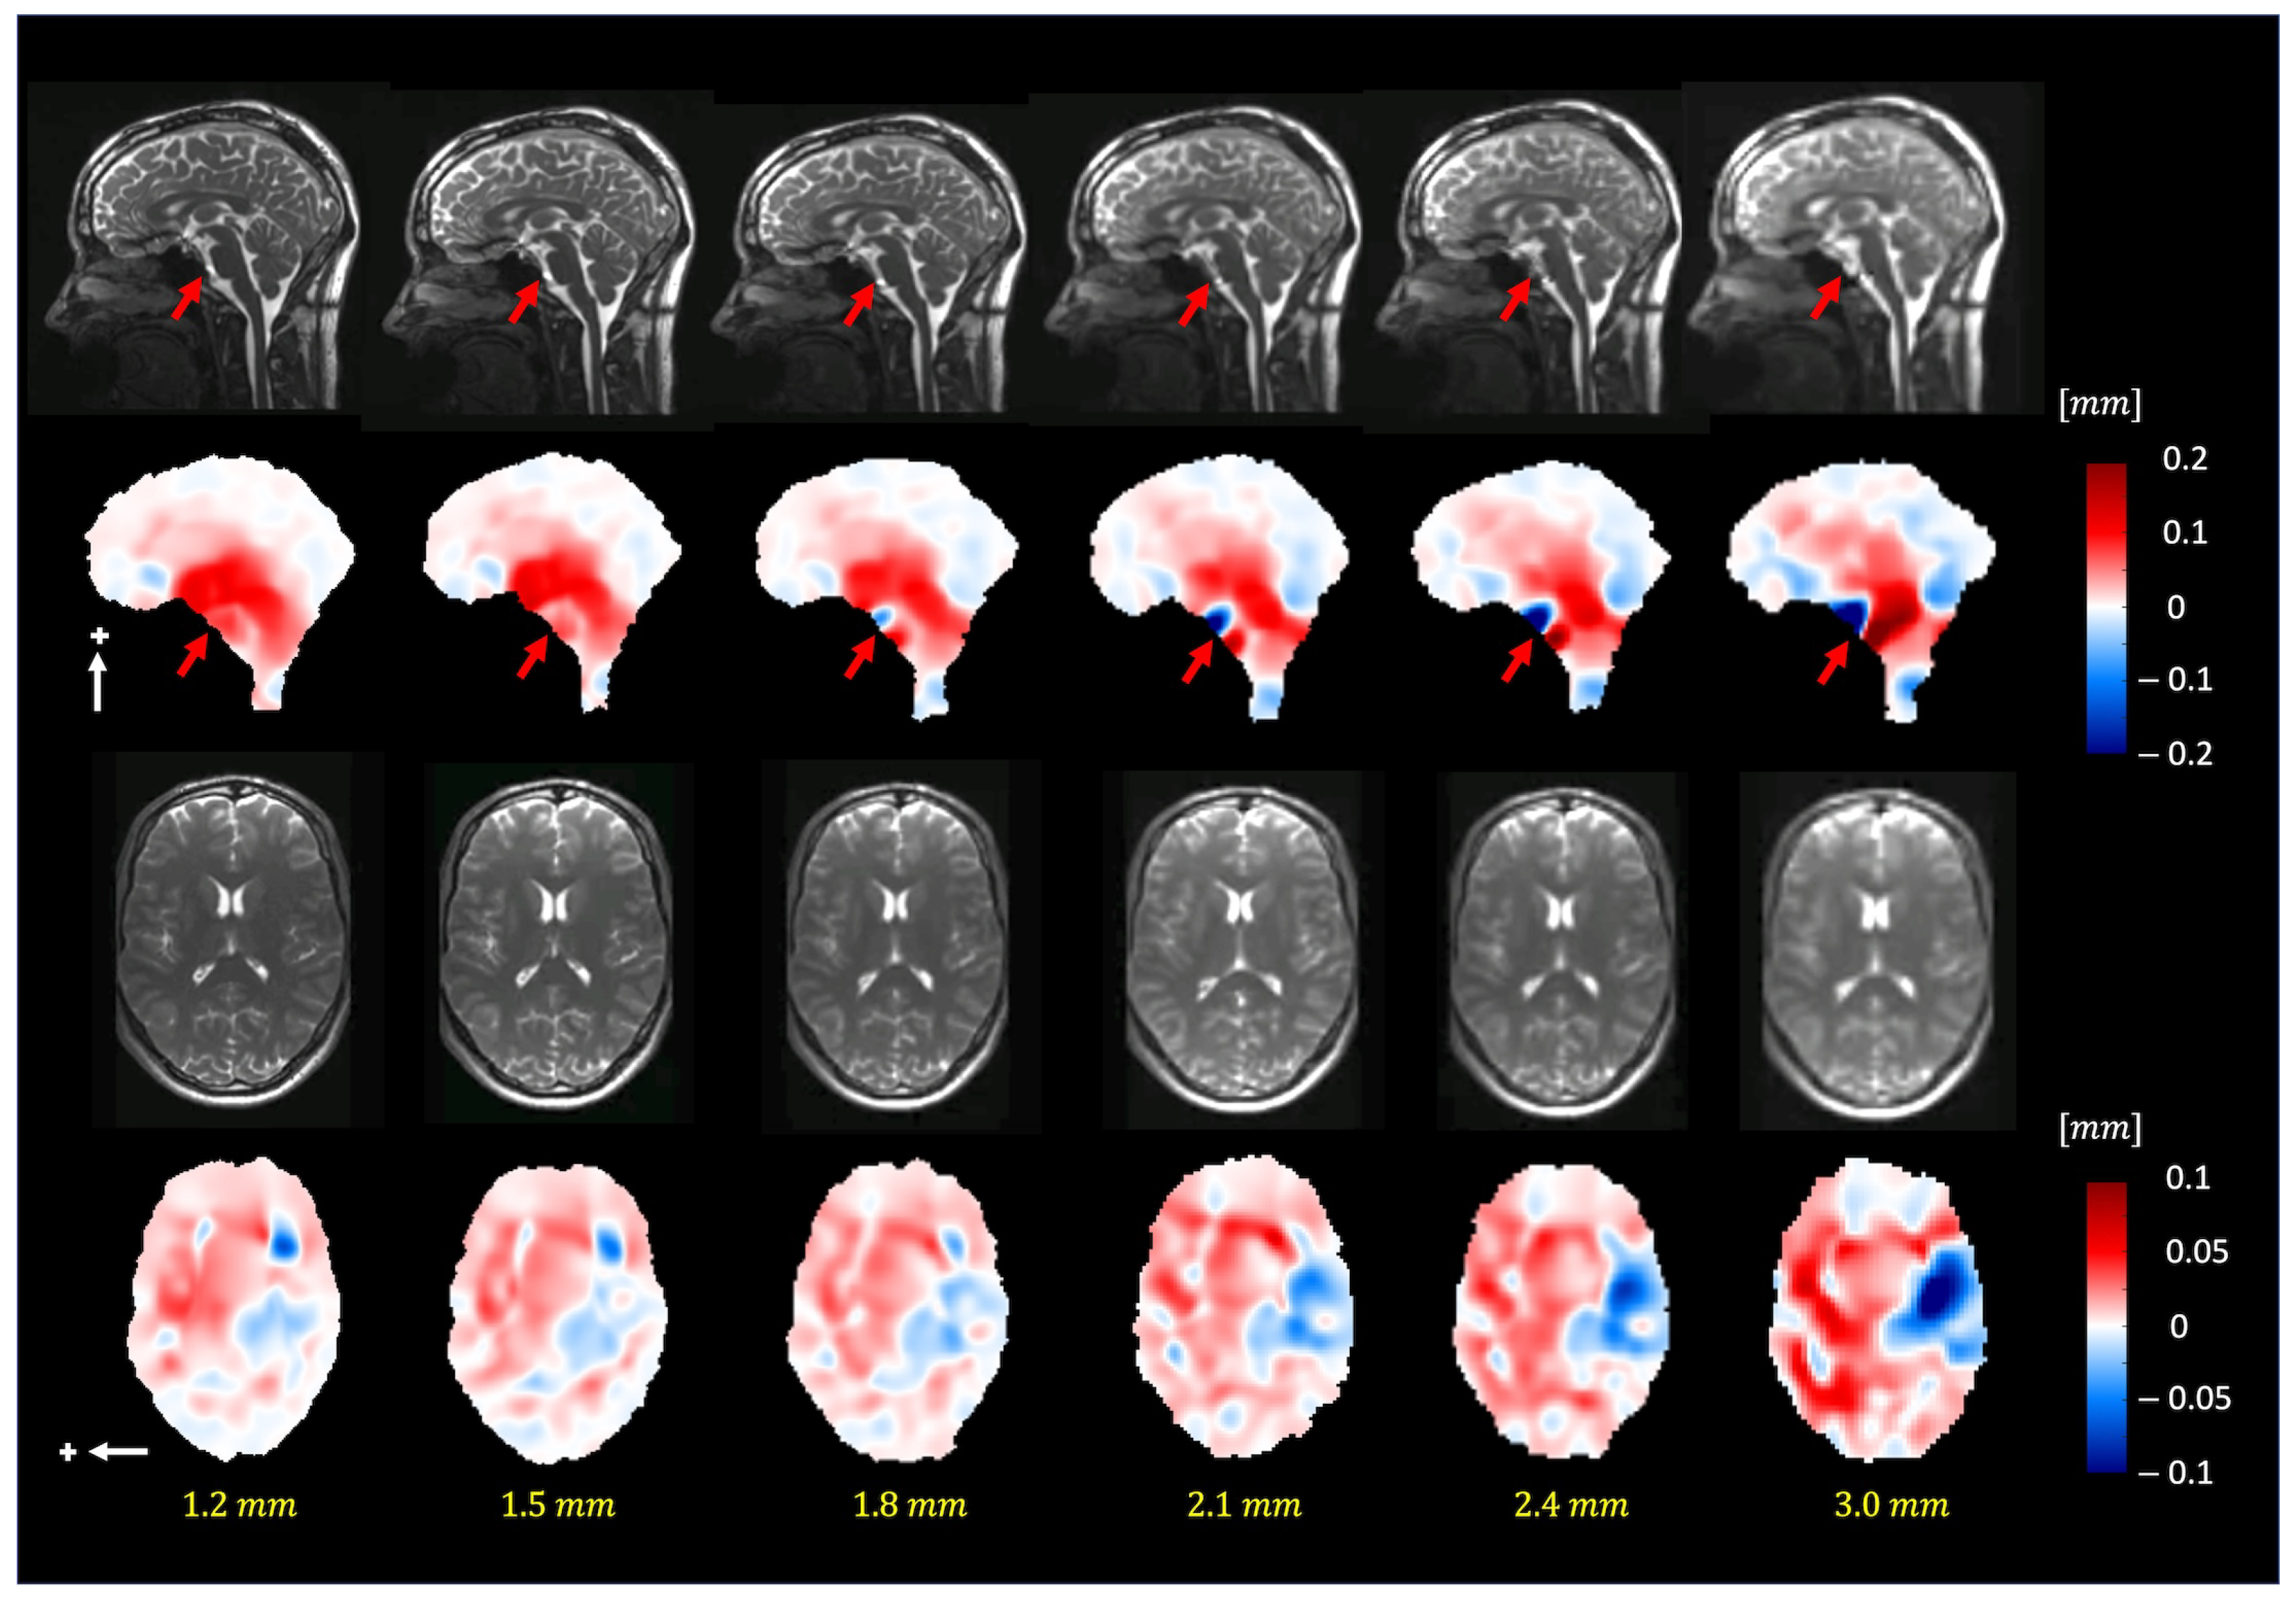

Figure 7 depicts the extracted motion field by 3D q-aMRI (Supplemental Video S6) for different isotropic voxel sizes (1.2–3.0 mm3). The extracted motion field remains consistent up to an isotropic voxel size of 1.8 mm. The red arrows in the sagittal plane point to the basal artery (Supplemental Video S7), which exhibits apparent motion (larger than 1.5 pixels) and, based on the phantom simulations, will result in an error in the estimated motion field.

Figure 7. The pulsatile brain motion in the sagittal (S/I direction, indicated by a white arrow) and axial (L/R direction, indicated by a white arrow) directions for different isotropic spatial resolutions. Plus sign represent the positive direction of motion. As can be seen, the algorithm can robustly estimate the motion field for different image resolutions (up to 1.8 mm isotropic voxel size). Note that the dark blue/red regions (red arrows) in the sagittal plane point to the basilar artery, which exhibits apparent motion (larger than 1.5 pixels).